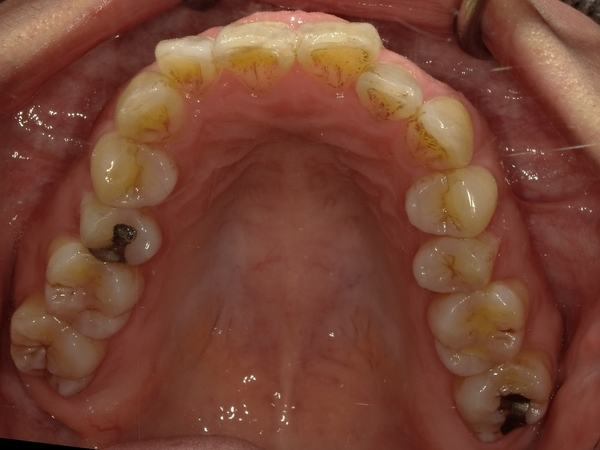

◯ご相談内容:歯がでたり引っ込んでいたりする◯矯正の種類:マウスピース型矯正「インビザラインGO」◯治療期間:17週間◯治療費用:44万円(税込)